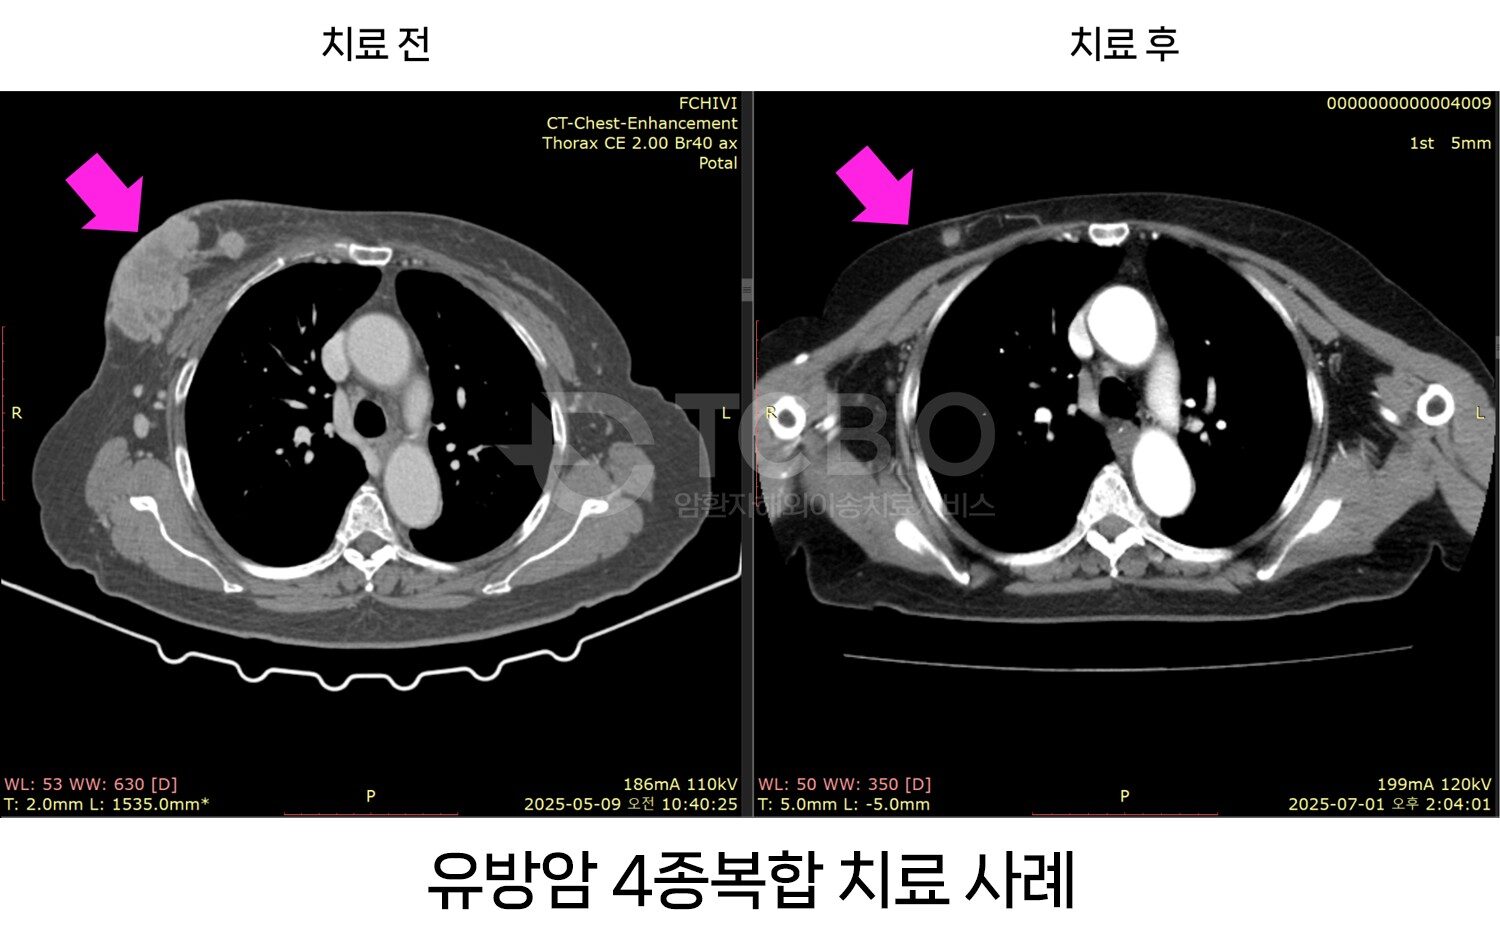

4종 복합치료를 통해 설암 4기 환자와 간암환자, 간문부담관암(Klatskin’s tumor), 유방암(삼중음성 유방암 포함)에 대해서 완전 관해 사례가 나왔다고 한다. 이 외에도 위암, 난소암, 대장암, 신장암, 방광암, 전립선암. 등등 우수한 치료결과 사례들이 지속적으로 나오고 있어 더욱 주목을 받고 있다고 한다.

이 복합치료는 표준치료에서 어려운 복막 전이, 뼈 전이에서도 치료가 가능하고, 부작용이 거의 없을 뿐만 아니라 치료 기간도 짧고 결과 확인도 4주째 확인할 수 있다는 가장 큰 장점이 있다. 심지어는 당장 중입자치료가 불가능 한 경우도 이런 복합치료로 호전시킨 후, 중입자치료 양성자치료를 시행하여 완치한 경우도 있어서, 표준치료만 고집해서 몸상태를 악화시키기 보다는 이런 치료방법을 고려해 보는 것도 바람직하다.